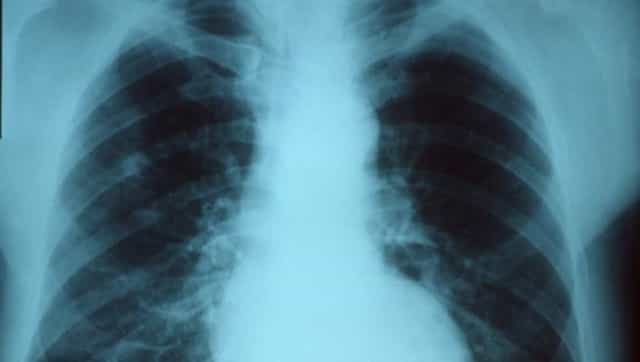

World Pneumonia Day was first observed in 2009 to raise awareness about and advocate for global action against the acute respiratory disease which claims millions of lives every year. The theme for World Pneumonia Day 2020 is “Every Breath Counts” which is apt given the added focus on the disease this year due to the COVID-19 pandemic. Impact of COVID-19 on pneumonia mortality According to statistics provided by Stop Pneumonia, a non-profit organisation, pneumonia claimed the lives of 2.5 million people in 2019, including 672,000 children. An editorial recently published in the American Journal of Physiology in early November 2020 suggests that the COVID-19 infection and pandemic is estimated to claim 1.9 million lives by 31 December 2020 and if all these deaths are categorized as lower respiratory infections by the Global Burden of Disease then it will increase the all-cause pneumonia mortality rate of 2020 by 70 percent. This, the article suggests, will bring the annual death toll due to pneumonia to a whopping 4.5 million. No other infection causes this immense a burden of death and that too globally. The impact of COVID-19 on how pneumonia is viewed, diagnosed, treated and prevented has been huge. How COVID-19 is linked to pneumonia Since the beginning of the pandemic, studies have shown that pneumonia is a complication of severe COVID-19. Pneumonia not only causes inflammation in either or both lungs but also leads to the build-up of mucus or fluid in them. This makes breathing even more difficult and worsens the disease further. Worsening of pneumonia can lead to acute respiratory distress syndrome (ARDS), which is a potentially fatal condition as it causes pulmonary fibrosis or the scarring of lung tissue. Further studies into COVID-19 associated pneumonia revealed that critically-ill COVID-19 patients who need oxygen support through ventilation are at an added risk of developing pneumonia. A study published in Science Translational Medicine suggests that when critically-ill COVID-19 patients are given high-flow oxygen from mechanical ventilation, it promotes the growth of bacteria like Staphylococcus aureus. The growth of such microbes in the lungs not only causes pneumonia but also leads to lung abscesses and injuries – the effect of which can last for a long time, making recovery all the more strenuous. What needs to change for pneumonia elimination As the aforementioned editorial indicates, the COVID-19 pandemic has revealed just how unprepared the global healthcare systems are — especially in low- and middle-income countries like India — to deal with wide-scale, rapidly escalating outbreaks of viral pneumonia as witnessed during the pandemic. From the lack of enough ventilators to the scarcity of pulse oximeters, the infrastructural deficiencies in dealing with pneumonia shed much-needed light on what is actually required to better deal with and eliminate pneumonia. Better investment in respiratory healthcare, whether it’s for equipment or grassroots awareness campaigns, is definitely the biggest need of the hour. Different types of pneumococcal conjugate vaccines (PCV) that can at least prevent bacterial pneumonia if not the viral ones are available across the world. Vaccination drives that ensure all children get vaccinated every year can reduce pneumonia cases to a great degree. It must also be noted that there is still no rapid diagnostic test for pneumonia and research-oriented towards the development of such tests would also prove to be of great value. Eliminating the risk factors of pneumonia is definitely another effective way of ultimately eliminating pneumonia, though this may be more challenging than other avenues to reduce pneumonia-related morbidity and mortality. According to the Global Burden of Disease, wasting or malnutrition and air pollution are two key risk factors for pneumonia, and eliminating such risks would require identifying at-risk populations, educating communities, equipping health facilities with pulse oximetry and oxygen support, and training medical staff to care for pneumonia patients better. All of this indicates that there is a lot to do before pneumonia caseload and mortality rates can even be controlled globally, let alone the total elimination of this deadly infection. So, while the COVID-19 pandemic has brought pneumonia into the spotlight, community leaders, state- and national-level policymakers and the global community of healthcare professionals and researchers need to join hands to make a difference. For more information, read our article on Pneumonia . Health articles in Firstpost are written by myUpchar.com, India’s first and biggest resource for verified medical information. At myUpchar, researchers and journalists work with doctors to bring you information on all things health.